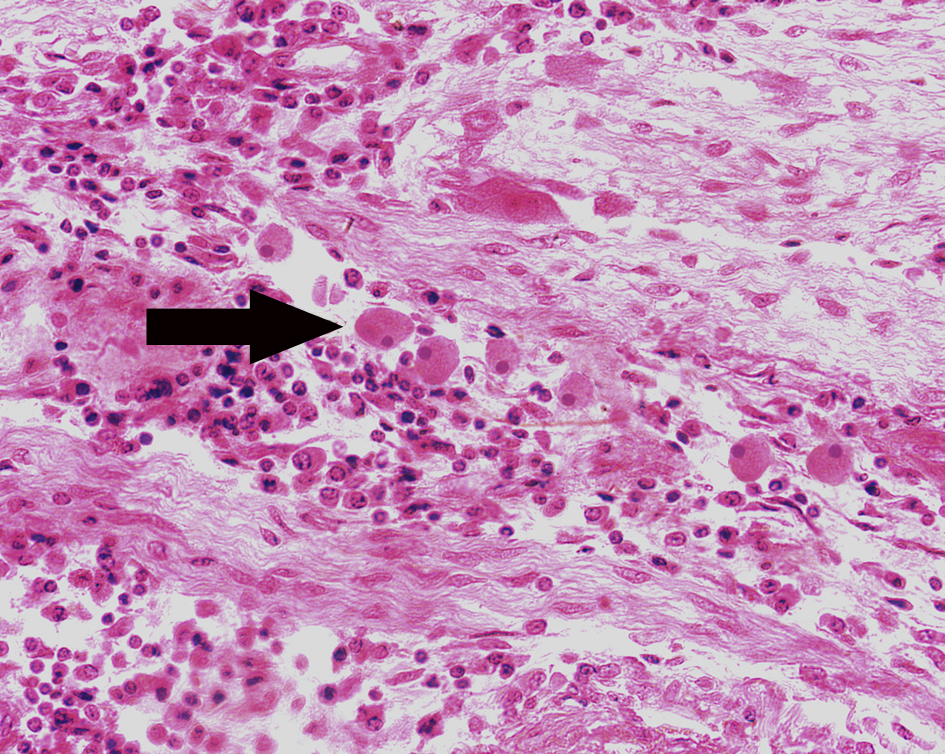

1.结肠阿米巴病